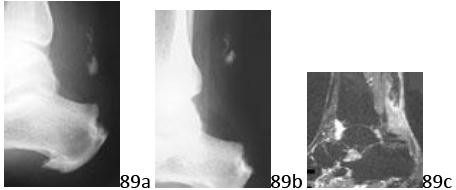

6. # 8a 8b A 35-year-old woman is involved in a head-on collision while driving. Initial radiographs are shown in Figures 8a and 8b. Injury to what vessel increases the risk for osteonecrosis of the injured bone?

DISCUSSION: The patient has a Hawkins type III talar neck fracture-dislocation with a risk of osteonecrosis ranging from 69% to 100%. Anatomic studies have shown that the artery of the tarsal canal supplies the lateral two

thirds of the talar body. The other vessels listed provide no significant contribution to the talus. The Preferred Response to Question # 8 is 4.